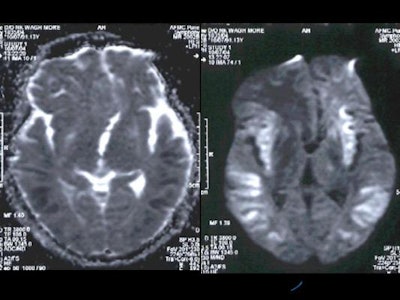

MRI was performed with the following sequences: TSE and gradient-echo T2 and FLAIR axial, TSE T2 sagittal and coronal, 3D Turboflash T1 sagittal with multiplanar reconstructions, and diffusion-weighted images with b-values of 500 and 1000 s/sq mm.

On diffusion-weighted images, there were hyperintense signals in the basal ganglia which appeared hyperintense on ADC maps, which implied that there was no restriction of diffusion in basal ganglia. However, the cortical grey matter showed hyperintense signals which appeared hypointense on ADC maps which indicated true restriction of diffusion [Figure 5].